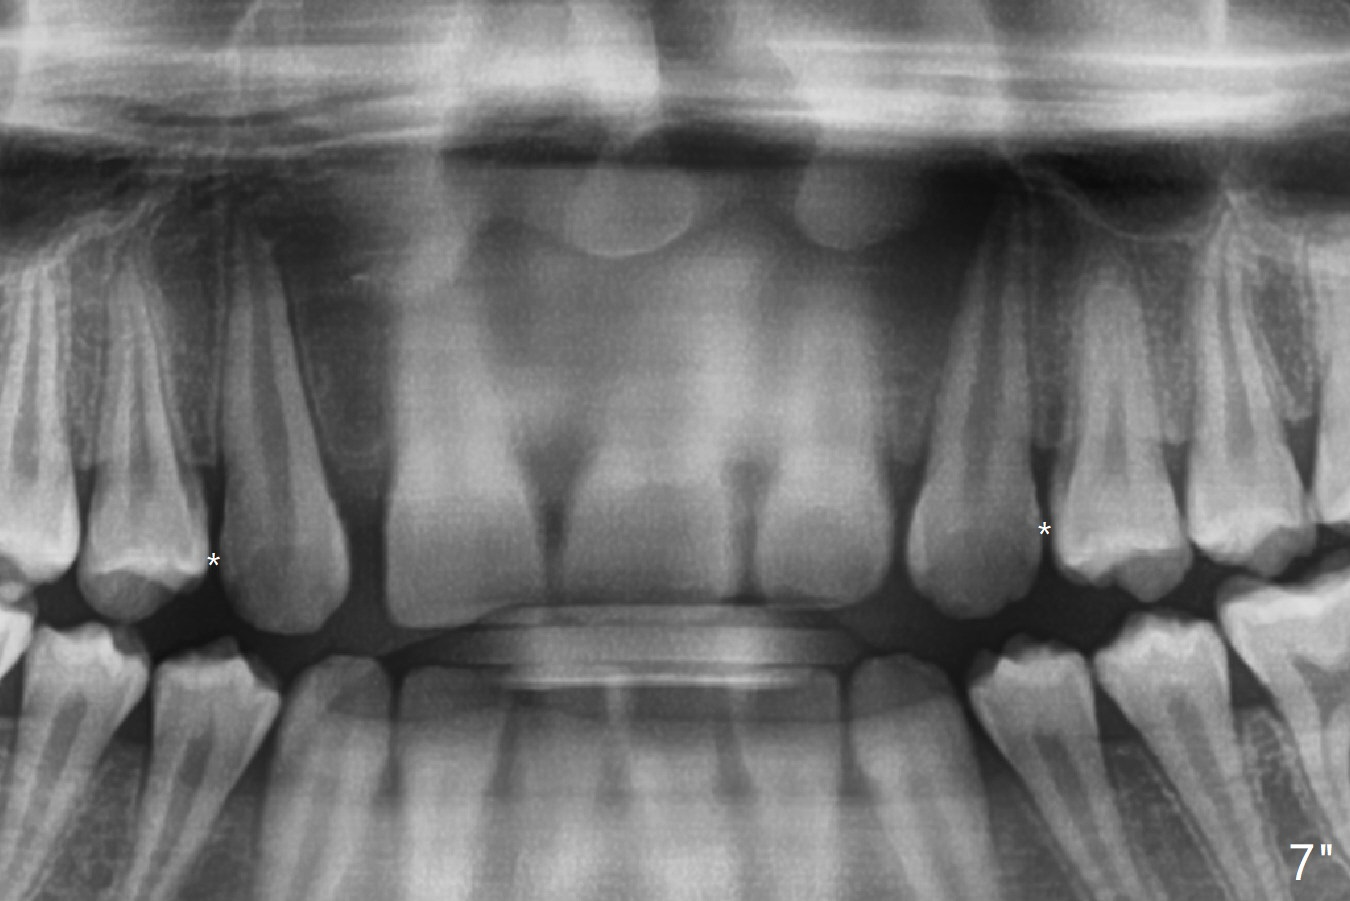

Bracketing for Congenital Missing Lateral